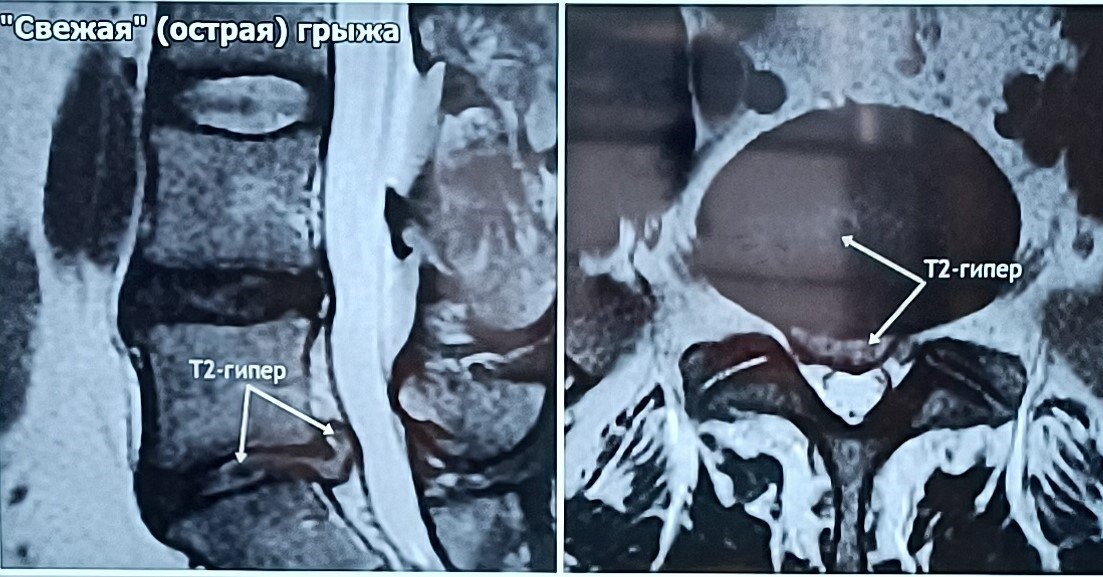

? Когда болит спина, мы привыкли винить во всем грыжу. Но часто МРТ открывает куда более глубокую картину, объясняя, почему стандартные упражнения не помогают, а боль становится хронической. МРТ — это золотой стандарт, который позволяет заглянуть внутрь и выстроить точный план спасения вашего позвоночника. Что же скрывается за снимками, кроме сухих цифр? ☑️ Жизнеспособность грыжи. Я смотрю не только на её размер, но и на структуру. На специальных режимах (STIR) видно, «светлая» грыжа или «темная». Светлая дает отличные шансы на резорбцию — её уменьшение без операции. Темная или застарелая требует уже другого подхода. ☑️ Скрытое воспаление (Модик 1). Бывает, что костные пластинки позвонков воспалены. Это та самая боль, которую невозможно «перетерпеть» или «закачать» в зале. ☑️ Состояние суставов Фасеточные суставы могут страдать от артроза или острого артрита. Это меняет всю биомеханику движения. ☑️ Костные «крючки» (остеофиты). Эти разрастания могут механически раздражать мышцы и